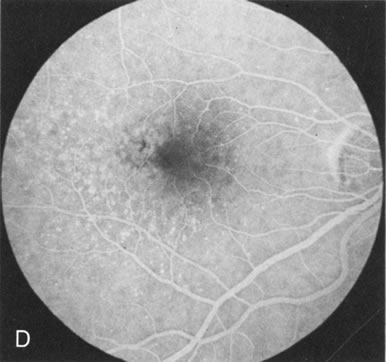

DOMINANT DRUSEN OF BRUCH'S MEMBRANE

There is no clear agreement as to what constitutes dominantly inherited drusen and what constitutes age-related degenerative drusen. There is a distinct group of younger individuals with bilateral, symmetric, uniformly small, round, discrete, yellow and white drusen. Histopathology demonstrates a nodular thickening of the RPE basement membrane, and these drusen have therefore been referred to as basal laminar, or cuticular, drusen.24

FA shows a characteristic pinpoint area of transmission hyperfluorescence corresponding to the drusen and reveals many more than are appreciated clinically (Fig. 12). Secondary changes such as pigment atrophy and dispersion, exudative and nonexudative detachments, and occasionally a neovascular membrane, will be revealed by FA (Fig. 12E).

Fig. 12. Dominant drusen of Bruch's membrane. The drusen appear as yellowish-white “blisters” predominantly in the temporal posterior pole (A). The angiogram shows many pinpoint areas of transmission hyperfluorescence typical of drusen, some of which have coalesced to form broader areas of hyperfluorescence (B). These drusen occasionally result in ingrowth of a choroidal neovascular membrane, such as occurred in this case over a 5-year period (C–E).